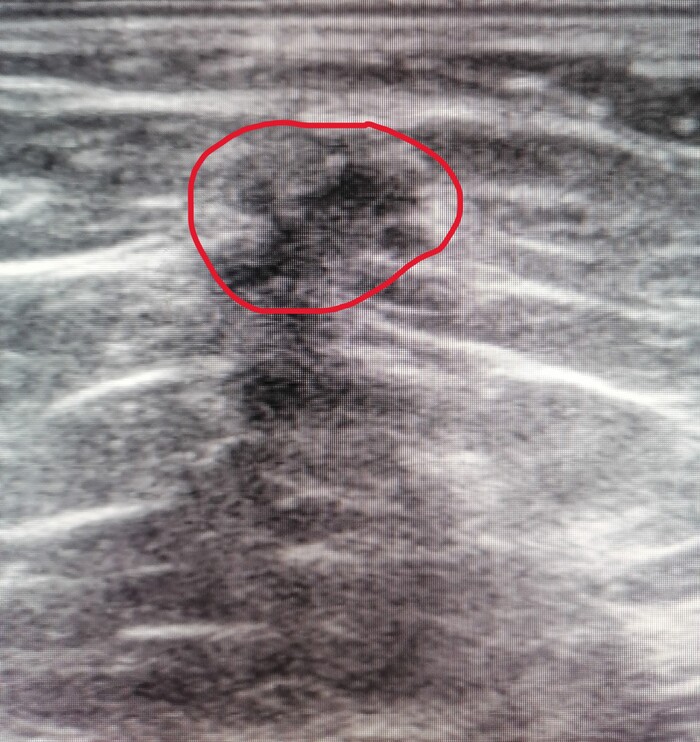

🔍 Улика №4 (ключевая): Там была история наблюдения за образованием в лёгком: 2 года назад — 2 см, год назад — 3.5 см с признаками роста, сейчас — уже есть метастазы в лимфоузлах.

Разгадка: У бабушки был карциноидный синдром — состояние, при котором некоторые опухоли (в данном случае в лёгком) выделяют вещества, вызывающие симптомы, похожие на климакс: приливы, потливость. Анемия, тромбоцитоз и повышенное СОЭ были «сопутствующим ущербом».